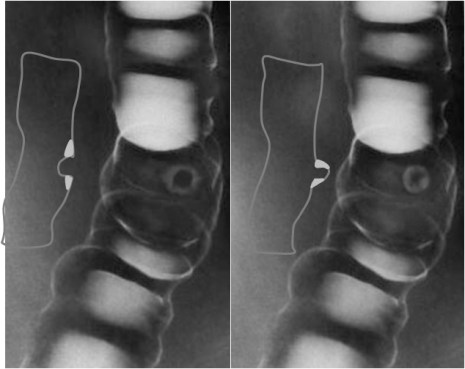

SIGNO DE HELLMER

Desplazamiento medial del borde lateral del hígado en la radiografía simple de abdomen por colección intraperitoneal (aunque también se ha descrito en colecciones extraperitoneales).

Esquema que muestra el hígado y algunas estructuras de vecindad. A la izquierda puede verse una colección (C) que se introduce entre el peritoneo y el borde lateral del hígado, al que desplaza medialmente. A la derecha, el esquema anatómico sin colección muestra el borde hepático no desplazado, delimitado por la grasa del flanco.